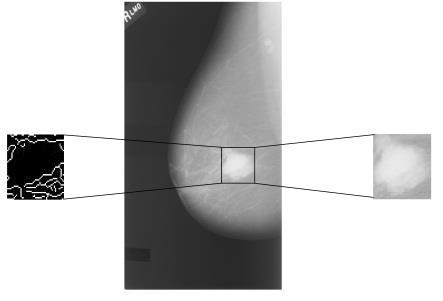

In this study, we propose a classifier which differentiates between benign case and malignant case in mammograms. The model takes into account simultaneously three data sources as inputs (Figure 3). (1) An image window covering the region of interest. (2) The canny filter applied to the same image window used in first input and we pass it as input. (3) The whole image considered as context surrounding the region of interest.

Figure 3. An area of image is extract from the region of interest and the same area is extract and filtered by canny

Accordingly, the classifier that we propose is formed by three subnetworks, the first one for the ROI, the second one for the filtered ROI and the third one is consecrated to the whole image, as illustrated in Figure 4.